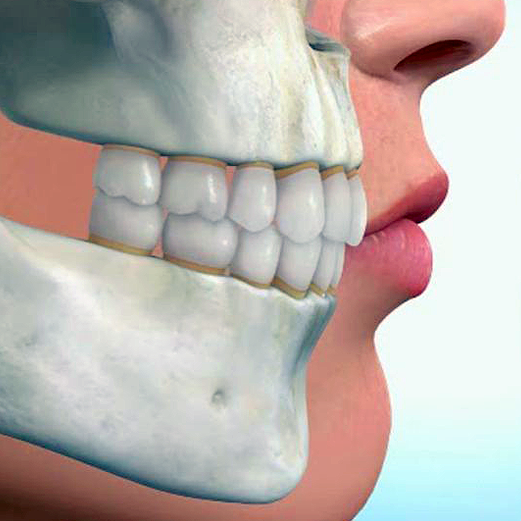

OCLUSÃO

É a área que diagnostica, previne e trata os problemas relacionados com más oclusões (posição incorreta dos dentes) e disfunções na articulação têmporo-mandibular (ATM). Estes normalmente traduzem-se em dor, cansaço e até mesmo degeneração das zonas afectadas.